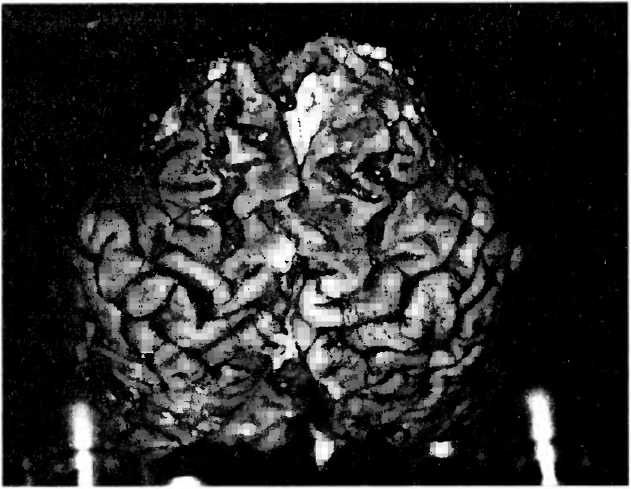

Болезнь Альцгеймера представляет собой наиболее часто встречающуюся форму деменции. Поскольку население в целом стареет, а возраст является важнейшим фактором риска для этой болезни, следует ожидать, что число жертв этой болезни в ближайшие 30 лет удвоится. Диагноз болезни Альцгеймера можно с уверенностью ставить в тех случаях, когда умерший пациент страдал деменцией и, кроме того, под микроскопом видны были характерные изменения мозга (рис. 28). Потому что существуют и другие формы деменции, которые только по виду мозговой ткани можно было бы с уверенностью отличить от болезни Альцгеймера.

Рис. 28. В серебряном окрашивании по методу Галльяса среза коры больших полушарий 85-летнего пациента с болезнью Альцгеймера под микроскопом видны два типичных поражения мозга: содержащие амилоид большие круглые бляшки между нервными клетками и клубки в нервных клетках, отмеченные черным.

Масштабная линия обозначает длину в 100 микрон.